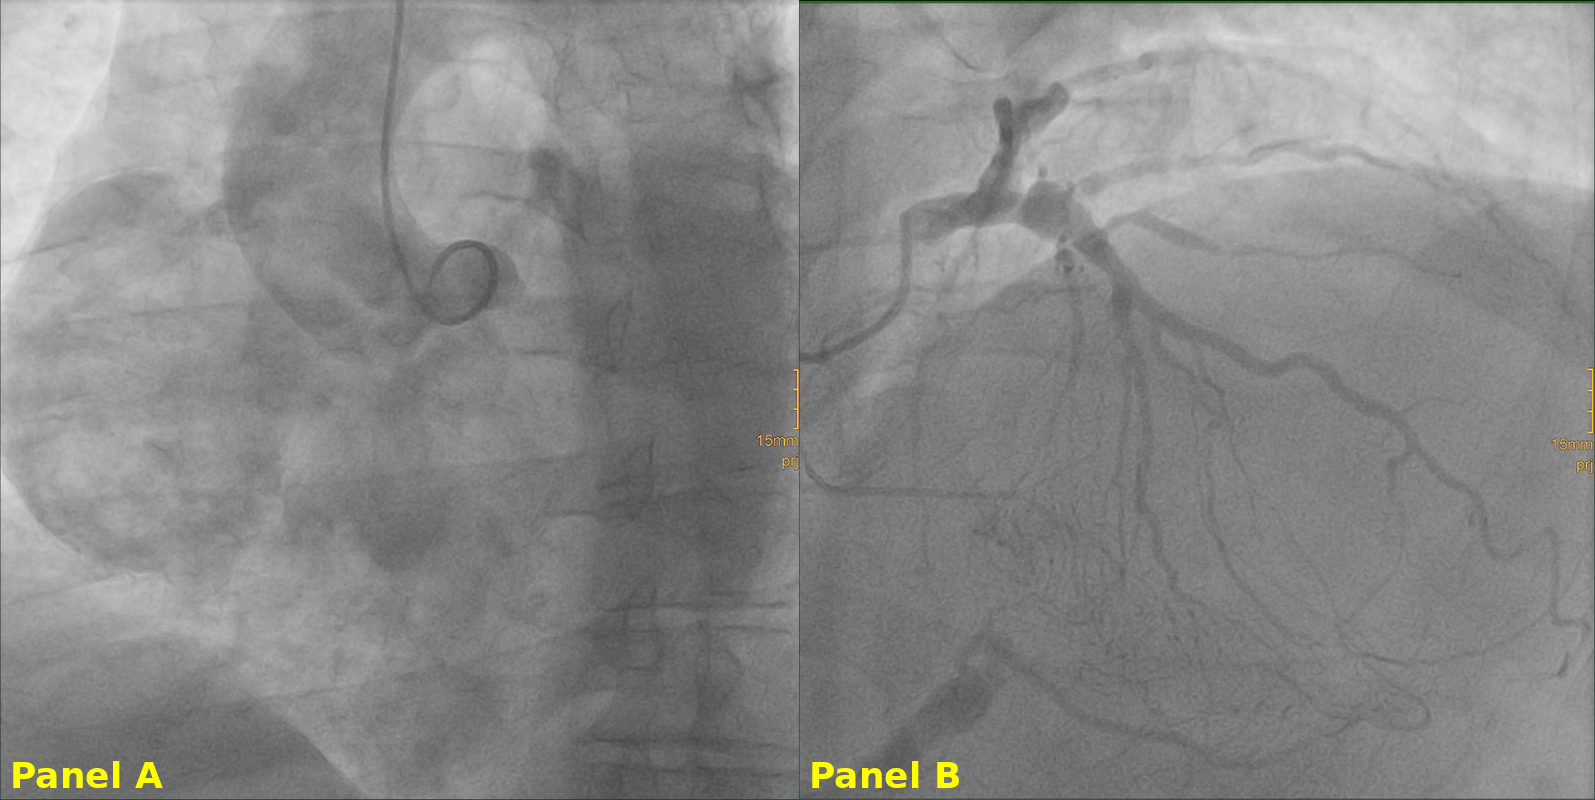

The patient remained hemodynamically stable and was initially discharged on optimal medical therapy. Coronary angiography revealed RCA occlusion with retrograde perfusion via left anterior descending artery collaterals. After multidisciplinary Heart Team discussion, conservative management was initially considered. However, due to aneurysm size and risk of complications, an endovascular approach was pursued.

The patient underwent percutaneous intervention under conscious sedation, utilizing dual arterial access (right femoral and left radial). The procedure included selective RCA catheterization, balloon occlusion testing proximal to the aneurysm, and deployment of a vascular plug at the RCA ostium.

Selective RCA catheterization was achieved, and a 0.014-inch guidewire was advanced into the aneurysmal sac. Balloon occlusion was performed proximal to the aneurysm to test for tolerance, followed by deployment of a vascular plug at the RCA ostium, achieving aneurysm exclusion. The patient remained stable throughout, with no clinical or electrical instability. Post-procedural imaging confirmed cessation of flow into the aneurysmal sac, without new compressive or ischemic complications.